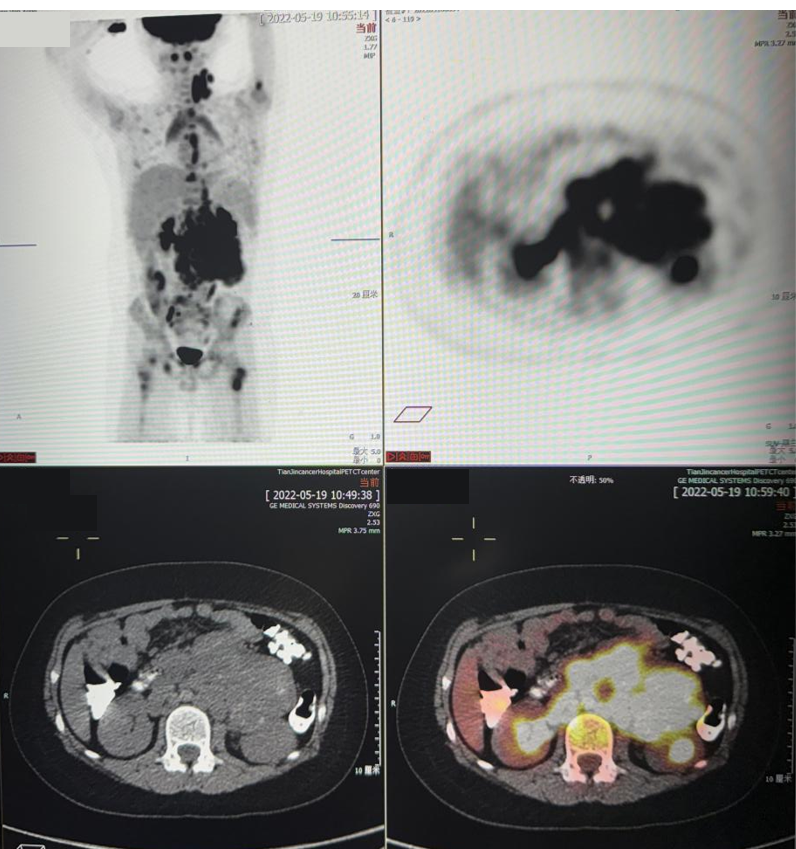

移植前评估PET-CT(2022.10.10):

1. 左腹壁手术瘢痕,考虑为术后改变;

2. 左侧中下颈、锁区,后纵隔食管周围,左下后胸膜下、双侧膈脚后、腹膜后腹主动脉及下腔静脉周围、肠系膜间、双侧髂总血管周围、髂脉区多发结节及肿物较前明显减小、减少,部分消失,此次PET显示放射性浓聚程度较前减低,提示病灶代谢较前减低,部分仍存活性;

3. 所见全身多发骨质密度不均伴第11胸椎压缩变扁,总体示病情较前好转。